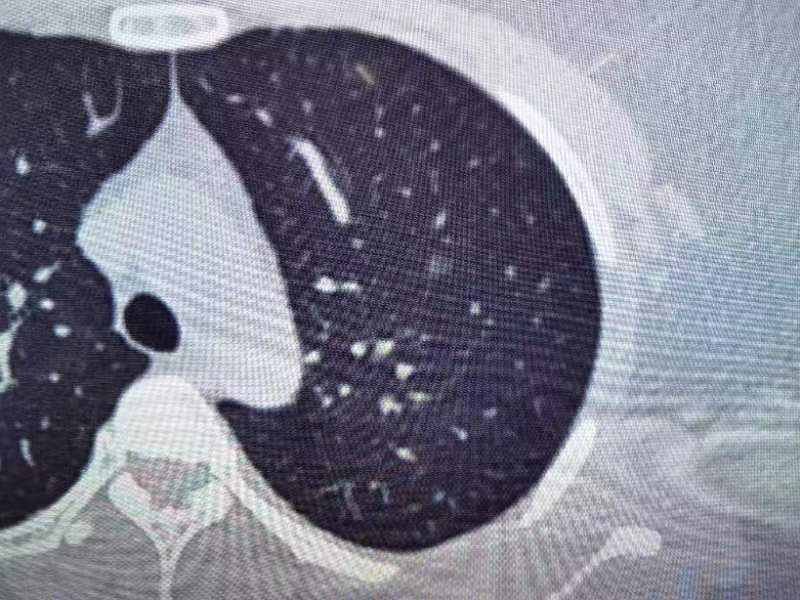

两年前,锁玉老师在我院体检胸部CT发现:左上肺磨玻璃小结节,靶扫描301im47及小结节分析左上肺见磨玻璃小结节影,平均直径约5. 5mm左右,CT值-631HU左右,考虑AIS可能,予定期随访观察。今年06月30至我院复查胸部CT提示:靶扫示左肺上叶(im123)见磨玻璃微小结节影,小结节分析提示:结节体积的明显增大,且有早癌指征。这样的检查结果,让锁玉老师为之苦恼,作为积极心态肯定是想要手术处理左上肺结节,但又担心自己的心肺功能差,不能耐受手术。

术前影像资料

邵丰主任及其团队医师们对锁玉老师进行了经过详细检查且全面综合评估,并进行了细致且严谨的术前准备,为了确保手术成功,采取了多学科协作的方式,为其制定了个体化的手术方案及康复方案。并循序进行气道管理方案,如心肺呼吸训练和抗阻训练,以提高其手术耐受性。锁玉老师完成相关检查,排除手术禁忌后,于7月10日在全麻下行胸腔镜肺叶部分切除术、胸腔镜下淋巴结活检术,术程顺利。手术进行得非常顺利,术后恢复得也很快。